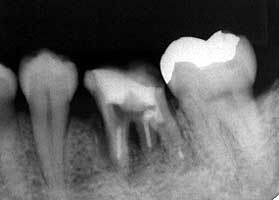

初診時パノラマ

|6穿孔による根分岐部病変

歯根のう胞と診断は、患者さんへの説明用だったのかも知れませんが、歯根のう胞は 存在しません。炎症の原因は根分岐部付近の穿孔でした。穿孔に対して貼薬処置を繰り 返していても何の解決にもならないけれど、適切な対処方法を大学で教わっていないの で仕方ないのかも知れません。

穿孔した空間部分に汚れが貯留するから炎症を起こす→汚れが貯留しないように空間 を閉鎖するというのが根本的な対応策だと思います。穿孔部分を大きく広げて汚れが 貯留しないようにするセパレーションも広い意味で穿孔の 完全閉鎖と同等の処置です。今回のケースは、穿孔部分が比較的根分岐部に近いのでセ パレーションを選択しました。